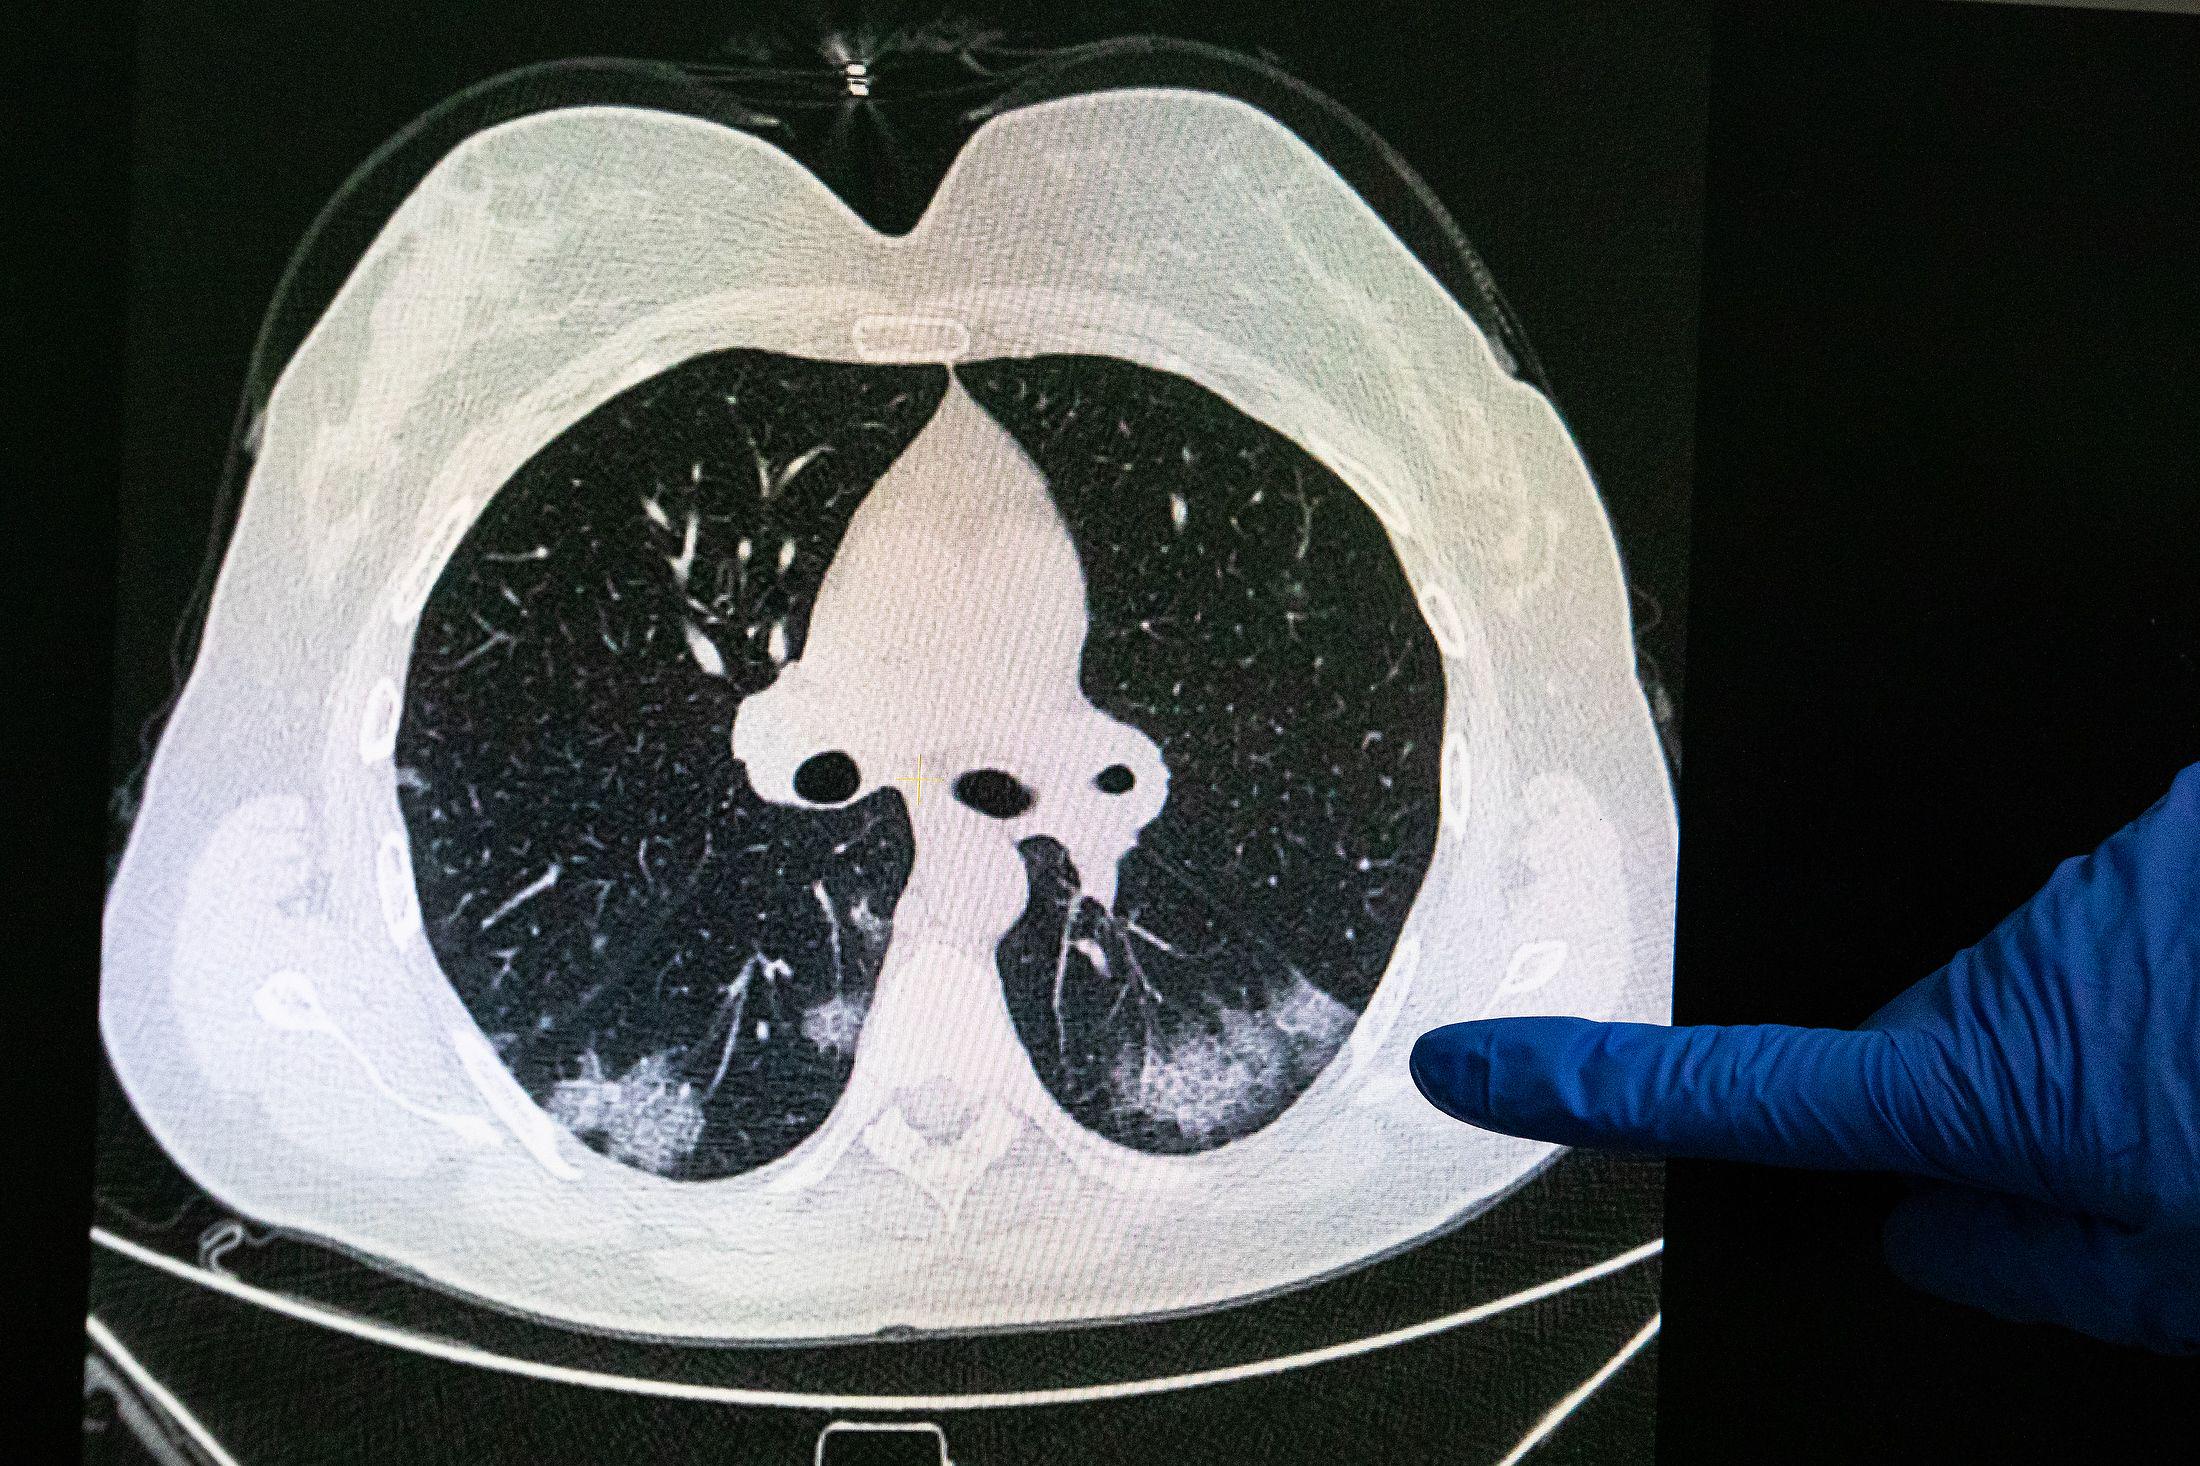

"Всё больше и больше специалистов понимают, что новый коронавирус - это не легочное заболевание, а острая вирусная инфекция, которая поражает кровообращение. Под кровообращением я понимаю и сердечно-сосудистую систему, и систему свертывания крови", - пояснил он.